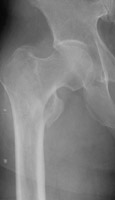

- Click on the image for a larger versionAAP radiograph of the left hip. This demonstrates an intertrochanteric fracture of the left femur.